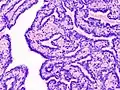

| Histopathology of intraductal papilloma of the breast by excisional biopsy. Immunostaining for p63 protein. | |